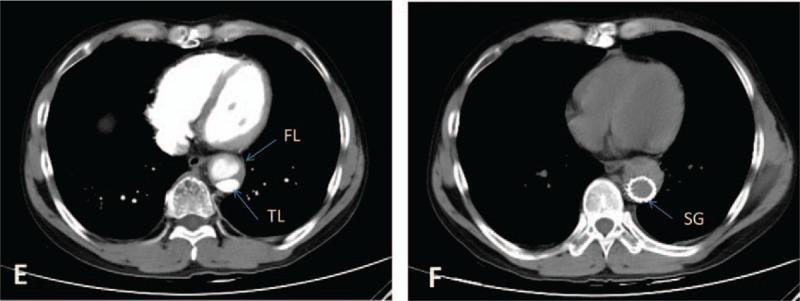

Computed tomography angiography revealed aortic dissection (DeBakey type III b) from the descending aorta to the distal abdominal aorta.

High-dose glucocorticoid therapy and immunosuppressive therapy have been used to control inflammatory reaction during acute period of Takayasu arteritis. Endovascular graft exclusion (EVGE) surgery was performed to cover the primary entry tear and re-expand true lumen during inactive stage.

计算机断层扫描血管造影显示主动脉夹层(DeBakey III b型),从降主动脉至腹主动脉远端。

在高安动脉炎急性期,使用大剂量糖皮质激素治疗和免疫抑制治疗来控制炎症反应。在非活动期进行血管腔内移植物置入术(EVGE)以覆盖原发破口并使真腔再扩张。